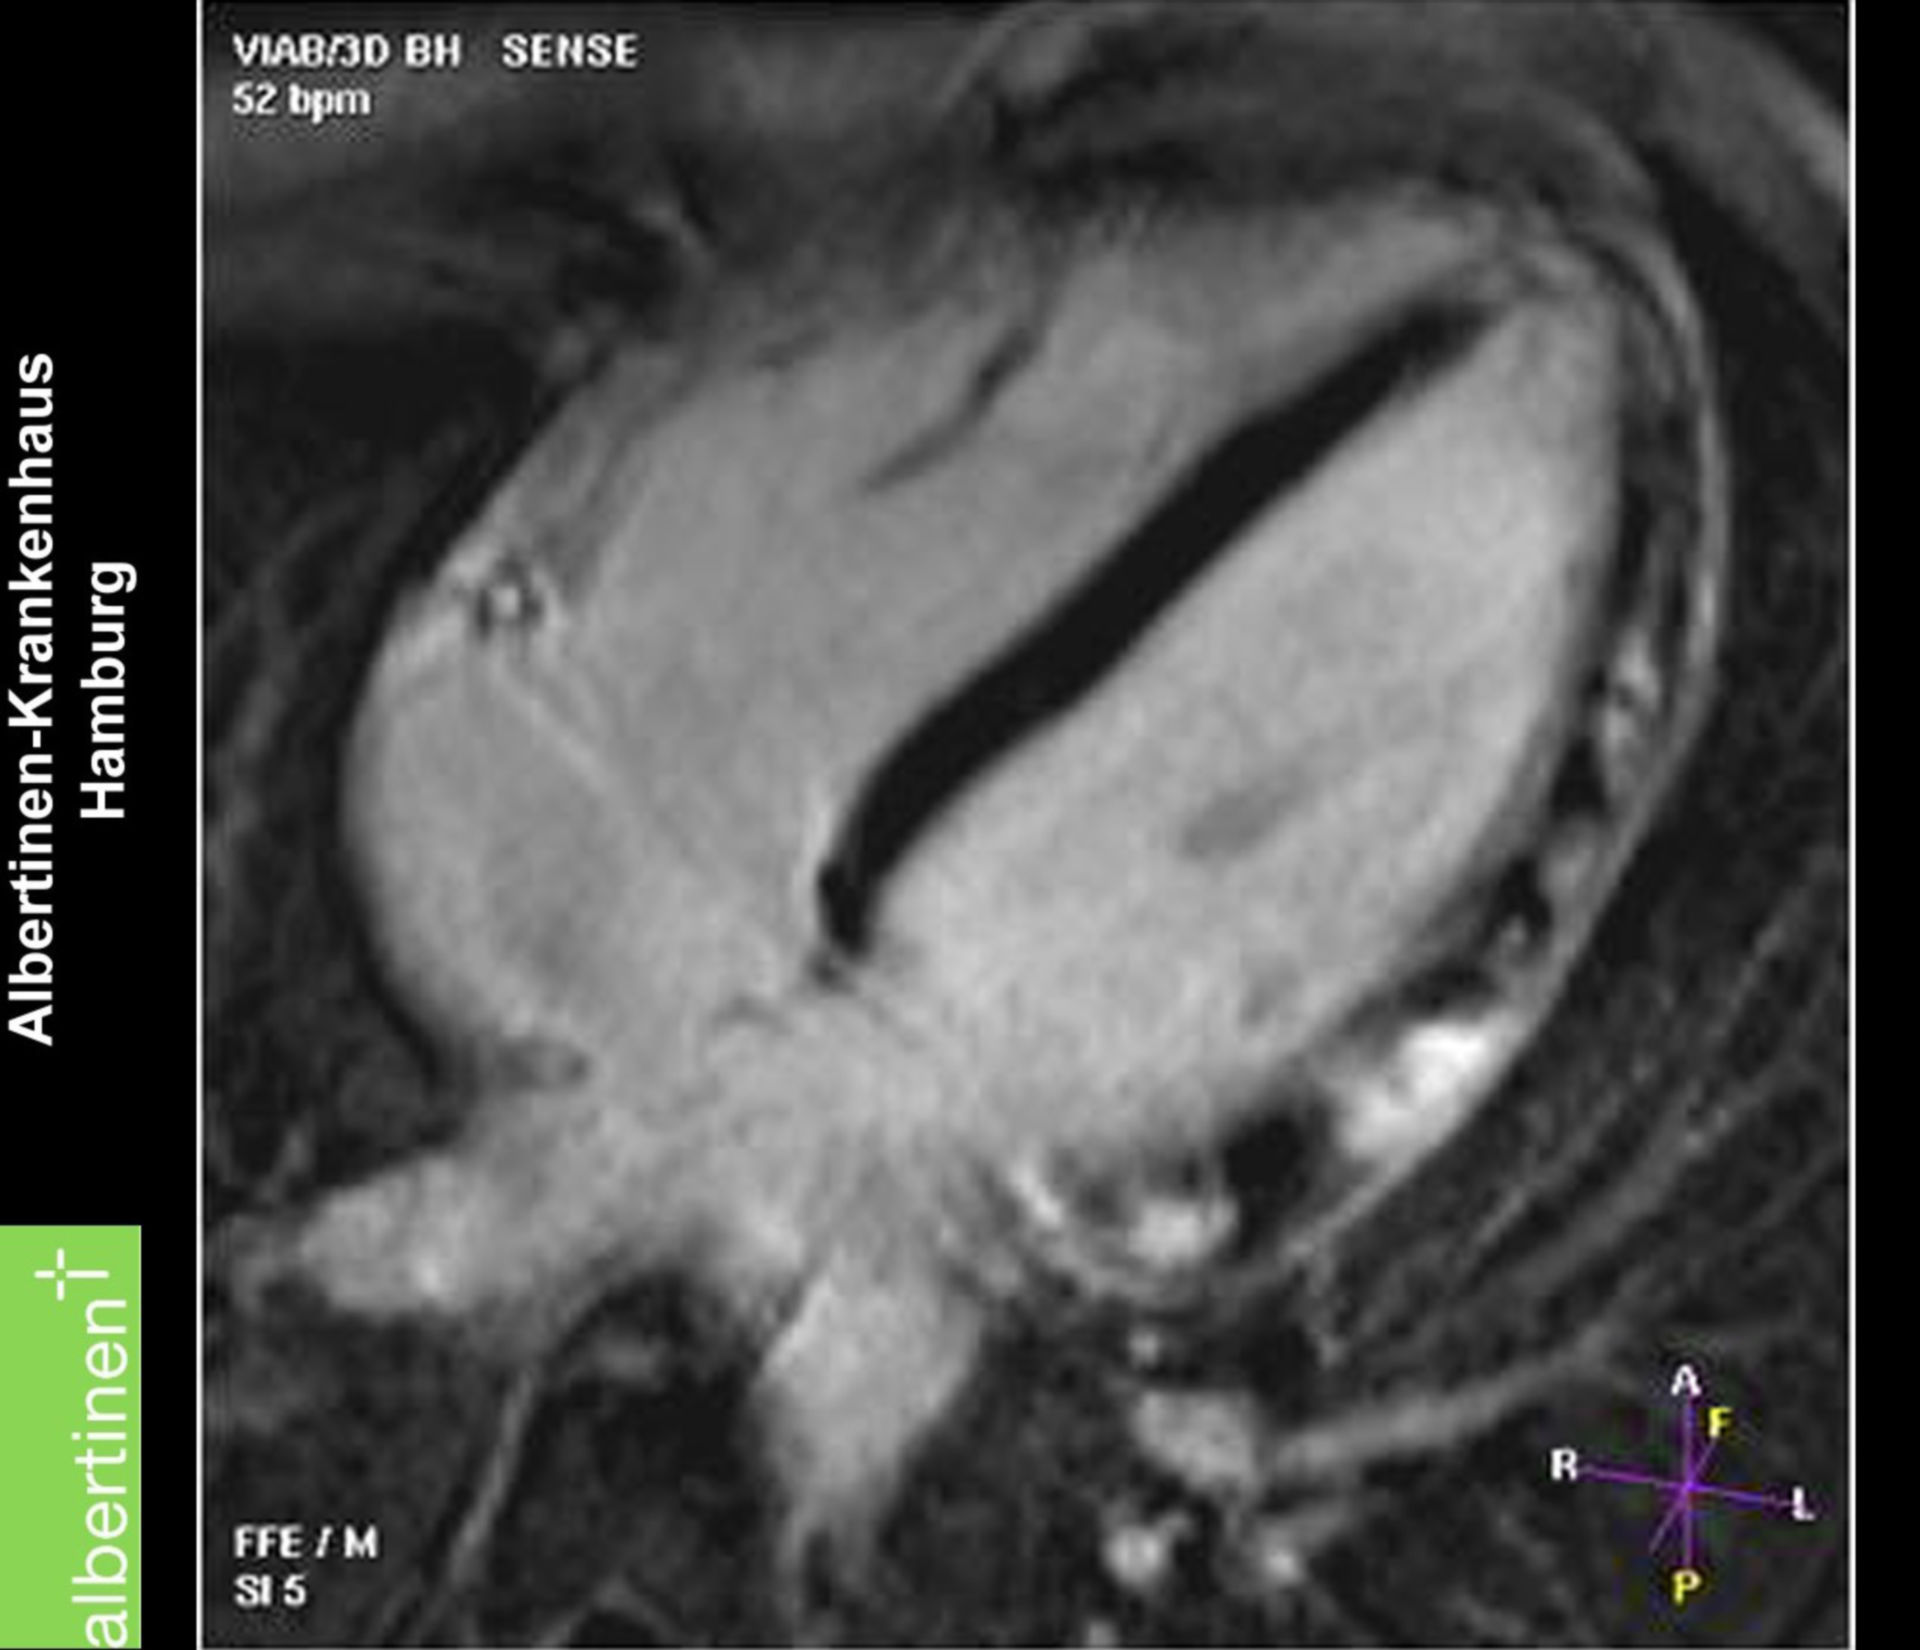

Myokarditis (MRT) – DocCheck MRT Schädel – DocCheck

Vorhofseptumdefekt (MRT) – DocCheck คอนโด MRT อิสรภาพ 2023-2024 / คอนโดติดรถไฟฟ้า MRT อิสรภาพ | คอนโดใหม่ 2566 / 2023, รีวิว คอนโด …